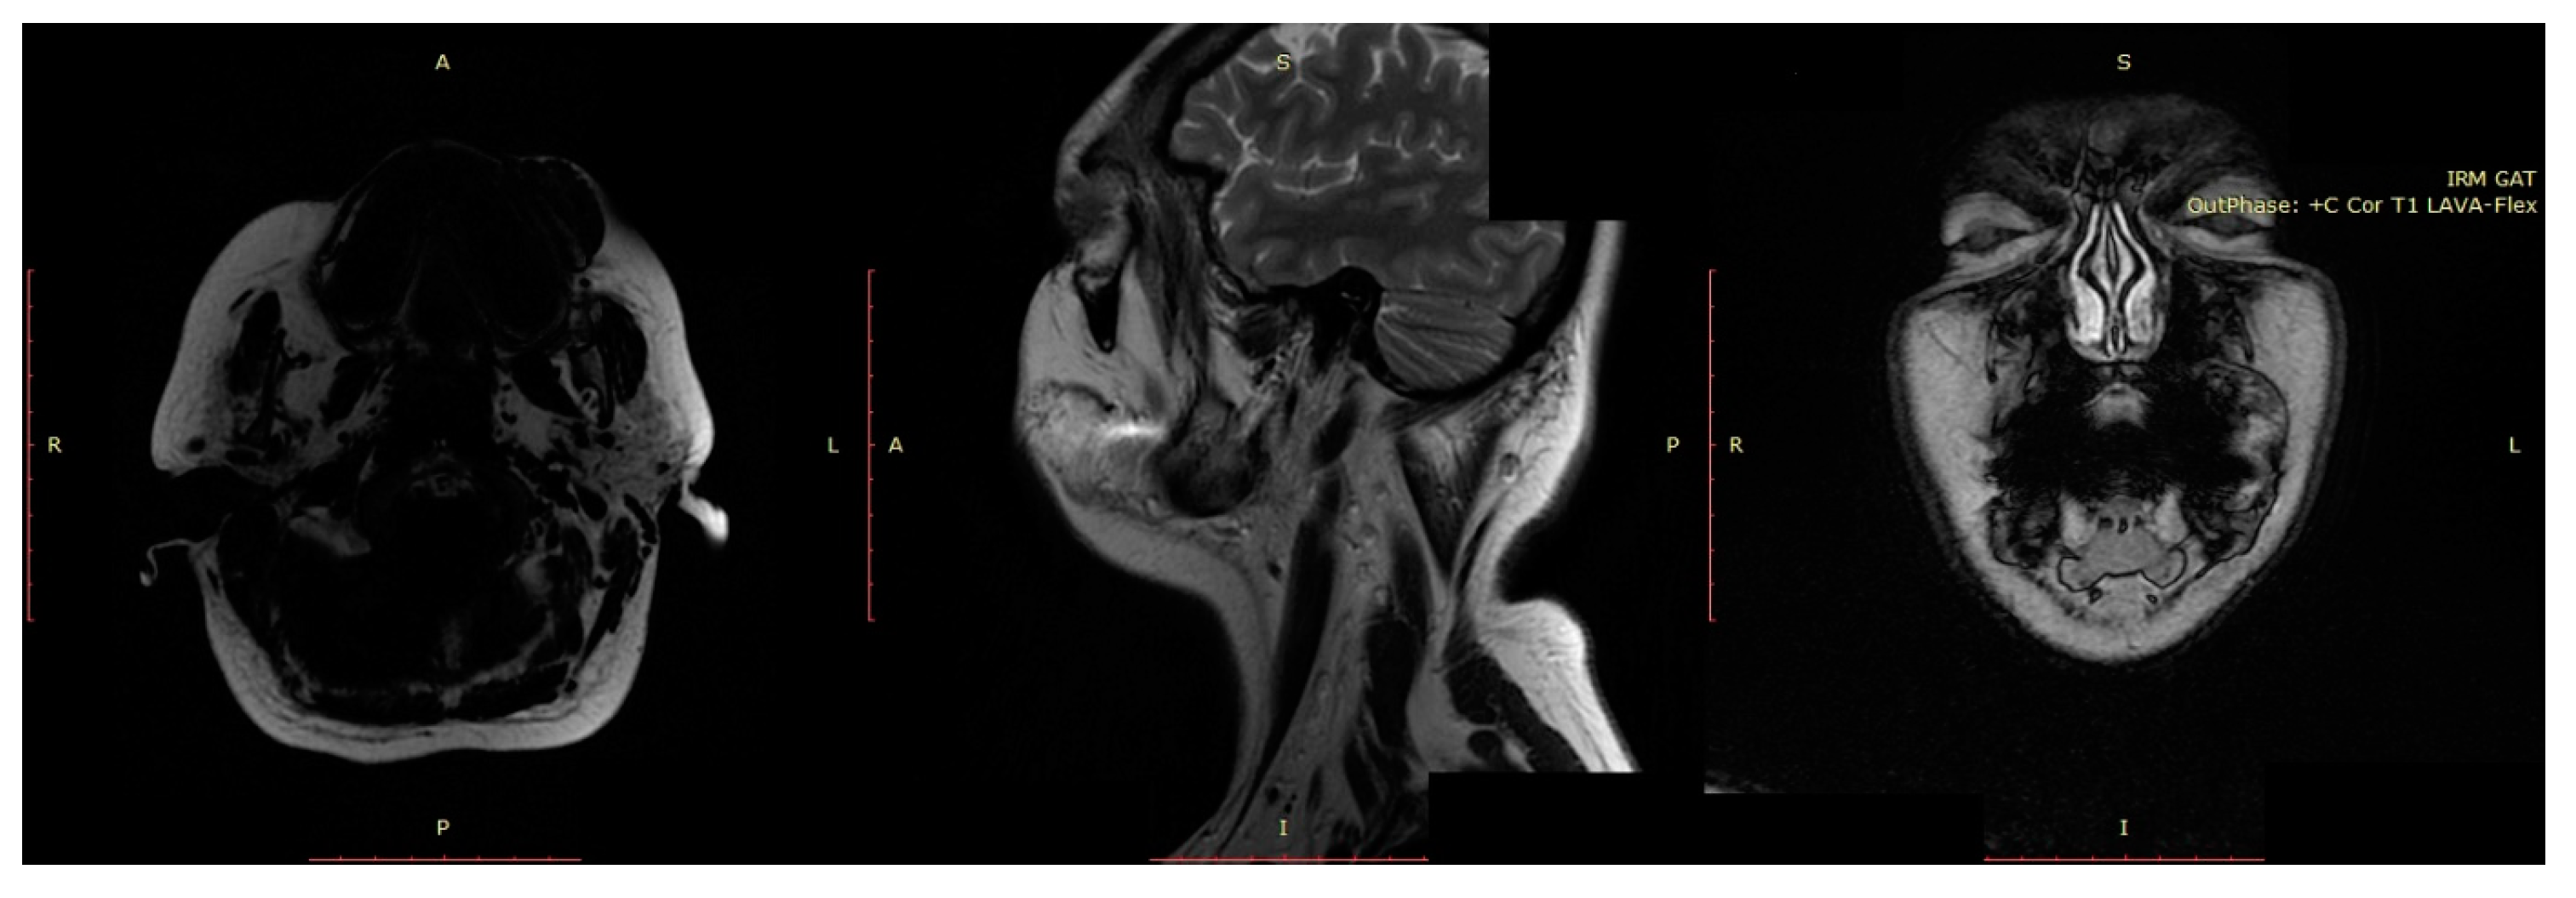

3.1.2. Diagnosis

3.2.2. Diagnosis

3.3.2. Diagnosis